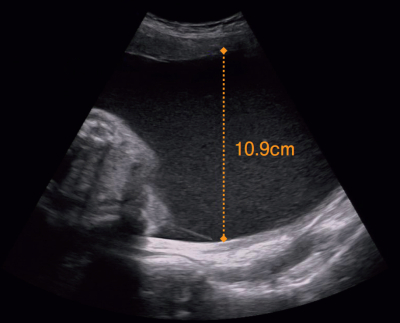

38 歳の初妊婦。妊娠 24 週に急激な腹囲の増大と体重増加を主訴に来院した。体外受精 - 胚移植〈IVF-ET〉で妊娠した。妊娠初期の超音波検査で 1 絨毛膜 2 羊膜性双胎と診断されている。超音波検査で両児間の推定体重に差を認めない。 1 児の最大羊水深度を計測した超音波像と両児間の隔壁を示す超音波像を別に示す。